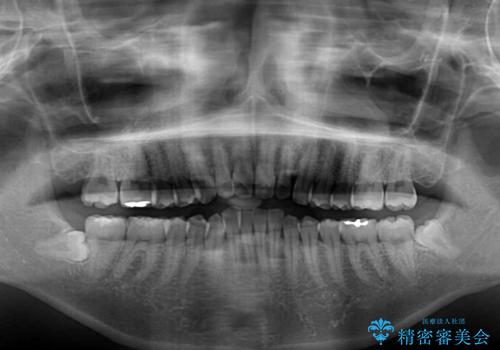

レントゲン写真での分析結果からは、抜歯矯正をするかどうか悩む境界線上でしたが、主訴が口元の突出感であったため、上下左右の第一小臼歯4本を抜歯して矯正治療を行うこととしました。